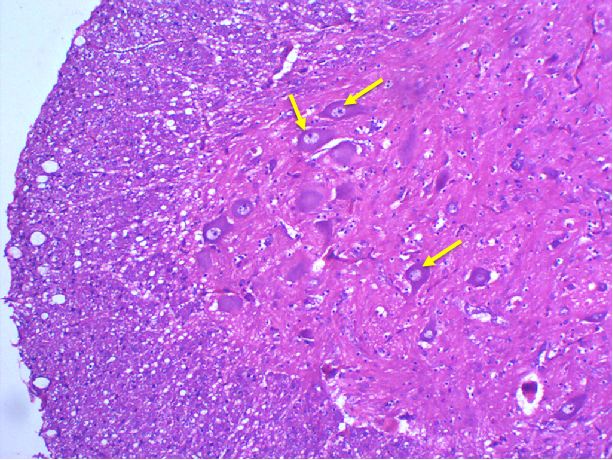

图3 脊髓灰质前角光镜图(HE染色)

可见脊髓灰质前角运动神经元胞体大,有多个突起;细胞核大而圆,着色浅,核仁明显;细胞质内有粗大的斑块状结构即尼氏体,强嗜碱性,染紫蓝色。尼氏体除分布于胞体,亦可见树突内,但在轴丘和轴突内无尼氏体。